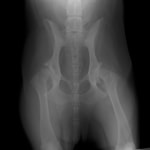

術前レントゲン

術後レントゲン

症例1 ゴールデン・レトリバー 7歳 避妊雌

後肢の跛行を主訴に来院されました。レントゲン検査にて、左右股関節の形成不全および重度の関節炎所見を認めました。THRに関しては適応年齢(約9カ月齢以降)の範囲にありますが、左右とも長期に及ぶ骨関節炎の進行により、大腿骨頭・寛骨臼ともに重度の骨変形を伴っていました。このような症例において、THRのカップの定着が悪くTHRの手術の成功率が下がるため、機能回復の面では劣りますが、症状がより重いと判断された左後肢の大腿骨頭・骨頚切除術を実施しました。今後は、リハビリテーションを行い、患肢の機能回復に努めると共に、反対側の大腿骨頭・骨頚切除術を検討していく予定です。

股関節形成不全は成長期に発症する進行性の関節疾患です。若齢期でのTHRの選択が機能回復において最も優れています。好発犬種のワンちゃんは成長期からの定期的な股関節のレントゲン検査をお勧めいたします。(詳しくは上記の診断を参照してください。)